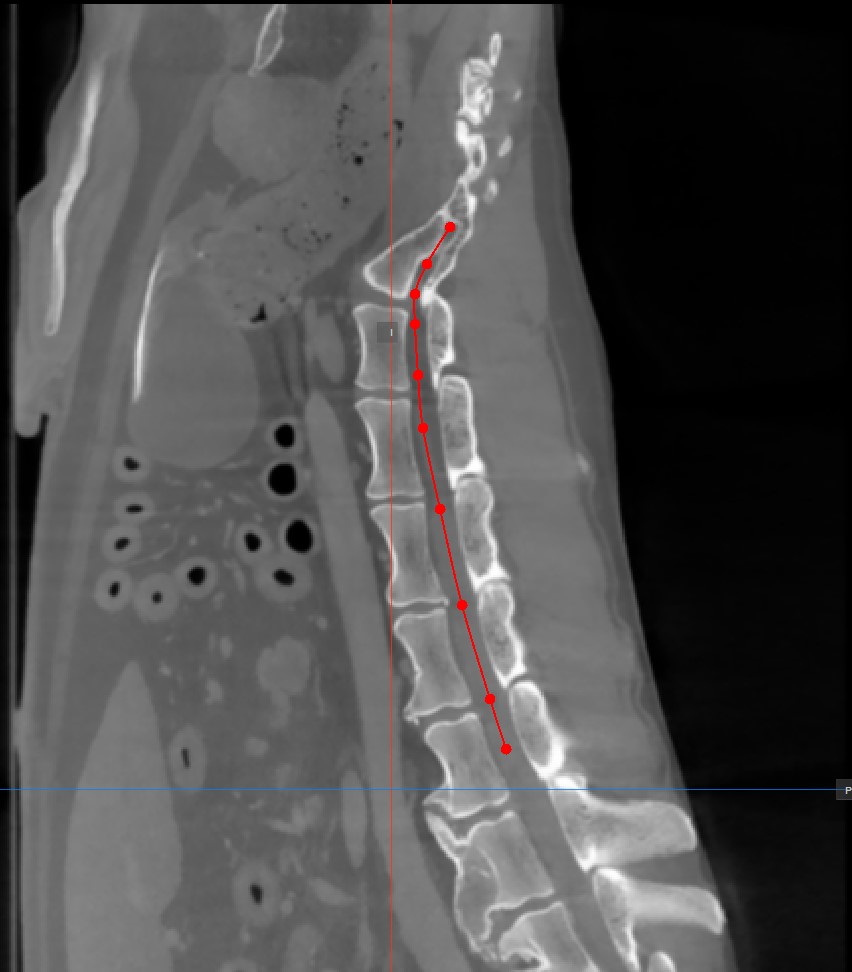

Die Curved MPR benötigt einen vom Benutzer gezeichneten Pfad, um die Querschnittsbilder zu erzeugen. Wählen Sie das Werkzeug CMPR-Punkt hinzufügen im unteren Bereich der CMPR-Ansicht, um den erforderlichen Pfad zu zeichnen.

Die Punkte, die den Pfad erzeugen, müssen in einem der drei verfügbaren Standard-MPR-Viewports auf der rechten Seite des Fensters platziert werden. Wählen Sie die am besten geeignete Ebene für die Anforderungen aus.

Mindestens zwei Punkte müssen auf den Bildern platziert werden, um den Pfad zu erzeugen. Die CMPR-Ansicht wird detaillierter, je mehr Punkte zum Zeichnen des Pfades verwendet werden.

Um den Pfad abzuschließen, aktivieren Sie das Werkzeug

CMPR-Punkt hinzufügenerneut oder doppelklicken Sie mit der Maus auf das Bild, nachdem der letzte Punkt des Pfades gesetzt wurde. Der Pfad wird nach der Fertigstellung grün markiert.